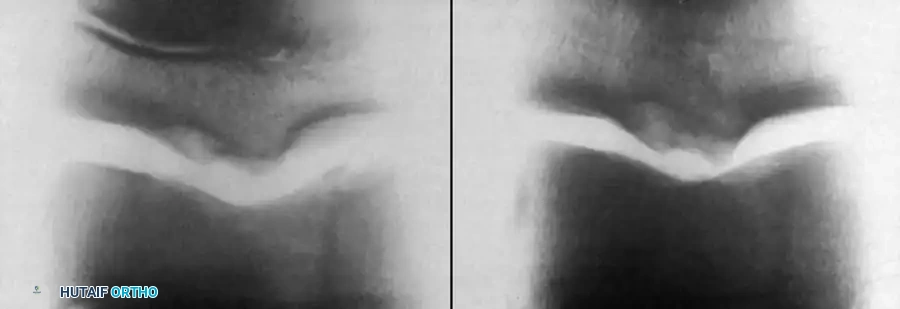

Natural History and Imaging

Bauer et al., in a long-term follow-up study (≥ 20 years) of 30 children with ankle osteochondritis, found that only one patient developed severe osteoarthritis. The vast majority experienced complete healing with only minor residual radiographic changes. This is in stark contrast to osteochondritis of the knee, where secondary osteoarthritis is a frequent complication.

Radiographic and MRI evaluation of osteochondral lesions of the talar dome, demonstrating subchondral separation and surrounding edema.